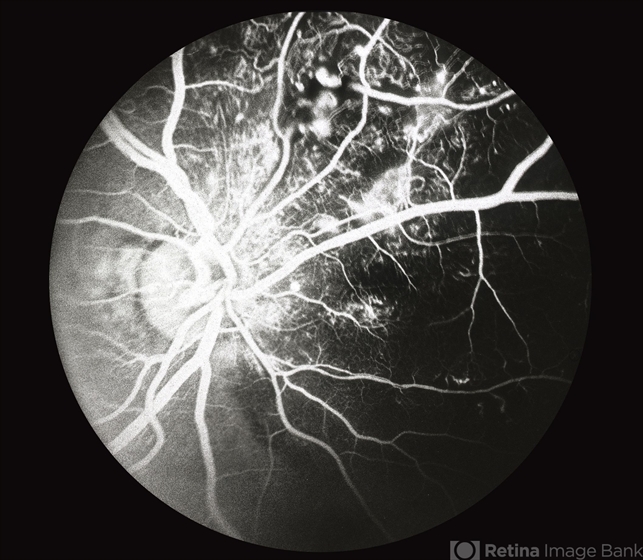

- Coats disease

- congenital retinal telangiectasis

- Flourescein angiogram with progressive filling of telangectatic vessels. The abnormal vessels become more prominent and the dilated aneurysmal-like vessels fill.